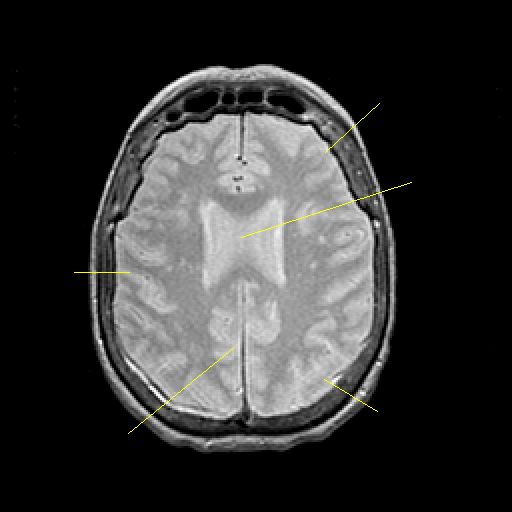

Proton density-weighted structural MR: Slice 35

Slice 35

Pointers

Labeled